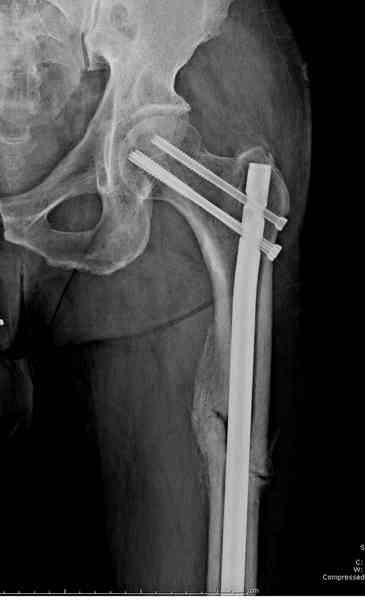

Здесь представлены снимки больного 65 лет, поступившего с диагнозом перелом

бедра после автоаварии.

В первый же день произведено антеградное штифтованием DePuy Trochanteric Nail.

На второй день (7) обнаружен пропущенный перелом,

Послеоперационные снимки